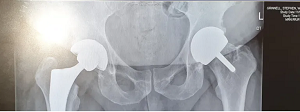

Day 43

My hospital consultant review was interesting as they had a look at my X-ray and remarked on a strange issue with my hips. The bone was regenerating around the implanted joint so essentially, my body had accepted the new joint